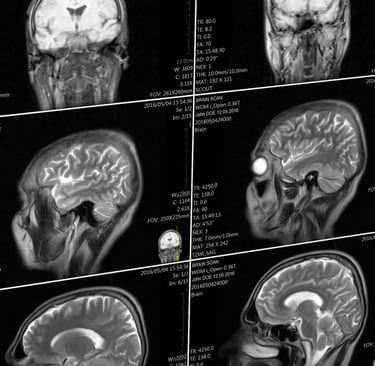

Microwave Effects on the Human Body

Introduction: Swanson et al. (1) examined 24 US Cuban embassy personnel exposed to an unknown directed energy source. They found that 21 of those examined had clinical findings similar to mild traumatic brain injury (mTBI). All 24 individuals reported audible and sometimes painful sounds during possible exposures. Hoffer et al. (2) examined a partially overlapping group of 35 embassy-related individuals, among whom 25 reported auditory phenomena and post incident symptoms along with 10 individuals who lived with the affected persons who did not report hearing sounds. These workers found that all 25 individuals hearing sounds had vestibular abnormalities; over half of these exhibited cognitive disorders. The ten individuals who did not report hearing sounds did not exhibit vestibular or cognitive abnormalities. Verma et al. (3) expanded Swanson's 2018 report to include 40 government employees describing acoustic experiences. These individuals had neurological symptoms suggesting mTBI. Significant brain structural abnormalities were documented using advanced specialized MRI imaging of this cohort (3).

"The analysis found that the patients who had been stationed in Cuba had less volume of white matter, which contains the parts of neurons that connect brain regions together, than the control groups. They had differences in their cerebellum to the control groups, and had lower connectivity in the auditory and visual networks of the brain (though not those involved in executive function).

Notably, Verma says, the patterns of changes in brain volume and in the cerebellum, were unlike the patterns of changes seen in any other diseases—they didn’t look like the changes seen in patients with traumatic brain injuries, for example, or other neurological conditions. “To the best of my knowledge, this is something unique to these patients,” she says. Seeing a new pattern, she says, is extremely rare.

The findings do indicate, though, that there are structural and functional changes in the brain that offer a potential basis for clinical symptoms. It’s a counter to some criticisms levied on the team’s prior paper that evaluated the neurological symptoms of this patient group, which included skepticism that their experiences weren’t just psychogenic. “The clinical element said there should be a problem in the cerebellum, and the imaging showed changes in the cerebellum. It’s an objective measure,” Verma says.

However, it’s not clear what the overall changes seen in this study mean clinically, for patient function, according to an accompanying editor’s note also published in the JAMA. It’s also not clear how significant the changes between the two groups are, says Gerard Gianoli, a neurotologist (someone who specializes in neurological disorders of the ear) at the Ear and Balance Institute in Louisiana. Gianoli says he’s more convinced by a 2018 paper that showed inner ear damage in those affected. The new paper, though, still provides important data. “It’s a part of the puzzle, and it adds a piece of information,” he says.

The changes in these patients, both in the brain and in the inner ear, could be caused by multiple different things, Gianoli says—this research doesn’t answer questions about the initial trigger. It may never be clear what happened, Verma says. “If you asked me, did something happen, I would say yes. But this doesn’t tell us how or why.” Americans reported hearing torturous sounds in Cuba—and now their brains seem changed.

NIH studies find severe symptoms of “Havana Syndrome,” but no evidence of MRI-detectable brain injury or biological abnormalities, Monday, March 18, 2024, National Institutes of Health (NIH)-https://www.nih.gov/news-events/news-releases/nih-studies-find-severe-symptoms-havana-syndrome-no-evidence-mri-detectable-brain-injury-or-biological-abnormalities

"Using advanced imaging techniques and in-depth clinical assessments, a research team at the National Institutes of Health (NIH) found no significant evidence of MRI-detectable brain injury, nor differences in most clinical measures compared to controls, among a group of federal employees who experienced anomalous health incidents (AHIs). These incidents, including hearing noise and experiencing head pressure followed by headache, dizziness, cognitive dysfunction and other symptoms, have been described in the news media as “Havana Syndrome” since U.S. government personnel stationed in Havana first reported the incidents...“It is possible that individuals with an AHI may be experiencing the results of an event that led to their symptoms, but the injury did not produce the long-term neuroimaging changes that are typically observed after severe trauma or stroke. We hope these results will alleviate concerns about AHI being associated with severe neurodegenerative changes in the brain.”